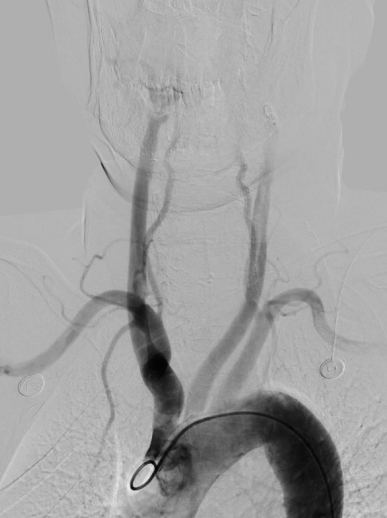

图片4.jpg

椎动脉狭窄                                                  椎动脉支架术后〔经桡动脉入路〕